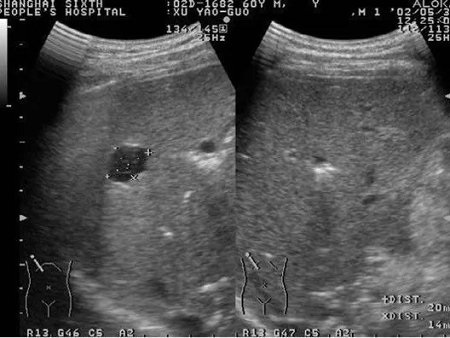

医生通过检查可诊断。但是如果小红点不沿皮肤表面弥散生长,而是向皮肤深部生长,皮肤表面可能看不出明显变化,但是却能发现高出皮肤的肿块或两侧皮肤不对称。这时可能会给医生的诊断带来困扰,这就需要借助彩超,在我们眼睛看不见的皮肤深面,了解肿块的性质,帮助医生更清楚的诊断(图4)。

▲ 图4

另有一些血管瘤在宝宝的其他部位,如肝脏、肠道等,外表皮肤可能会伴有多发的皮肤血管瘤,或者看不出异常,也不会有疼痛等,这就需要通过彩超、CT等检查及时发现(图10)。

▲ 图10